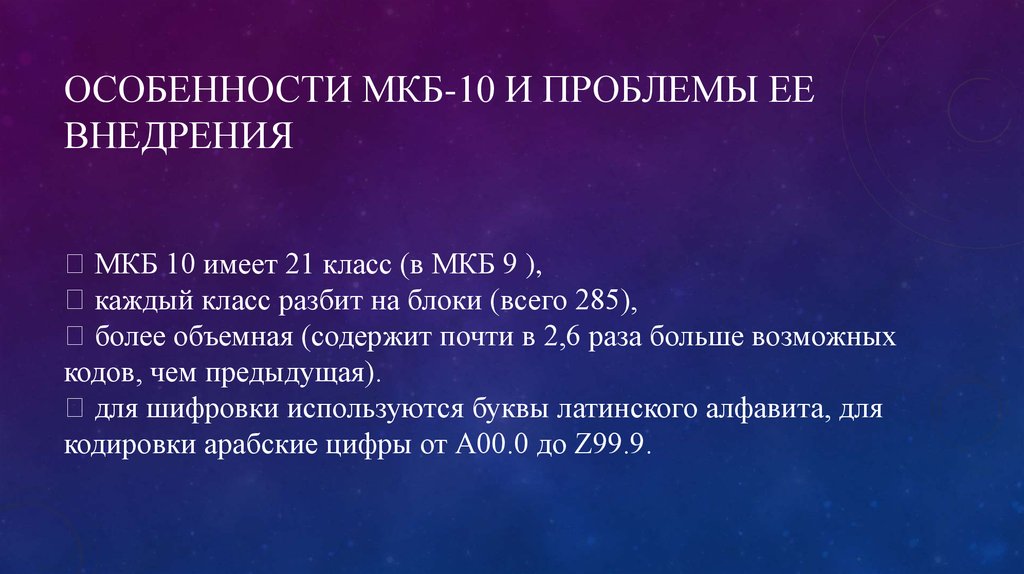

Код мкб 10 атерома головы

Код мкб 10 атерома головы 109 фото